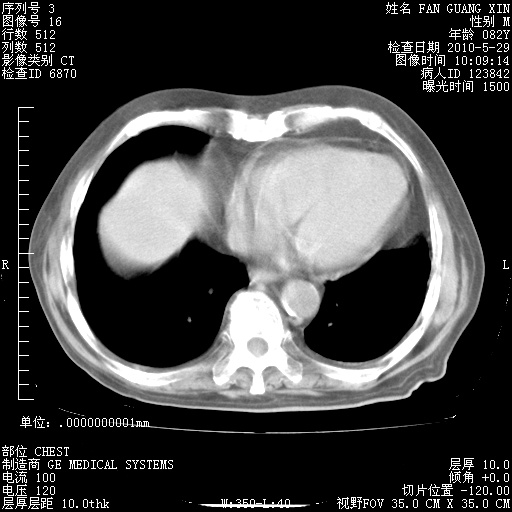

再治疗10天后的肺部CT 纵膈窗

阅读此次胸部CT,肺间质渗出性改变较入院时有吸收。目前从体温、白细胞、中性分叶明显增高,肯定存在细菌感染(发生医院感染哦,若无消化道及泌尿系统等感染的依据,肺部感染可能大)。若你院头孢哌酮舒巴坦钠耐药率较高,同意你的方案,若48小时体温仍高,可考虑使用碳青霉稀类抗菌药物,同时可予超声雾化、注意滴数时加大液体量。白蛋白33.30g/L较低哦,需加强营养等支持治疗。